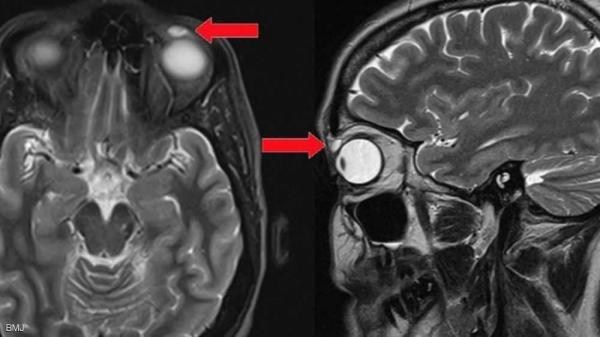

عاشت 30 عاما بشيء غير مريح في عينها.. ثم جاءت "الصدمة"